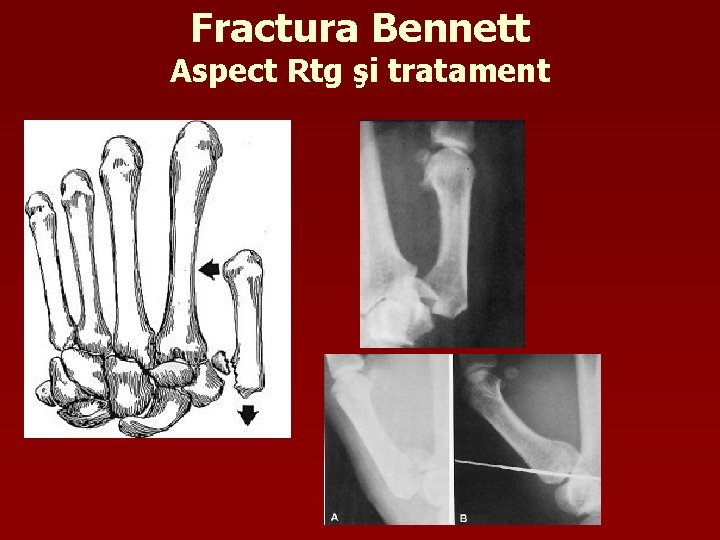

Clasificarea fracturilor metacarpianului I Bennett – fractură-luxaţie Rolando – fractură intraarticulară

Fractura Bennett Aspect Rtg şi tratament